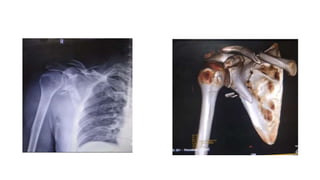

• Ganz and Noesberger 1975 – floating shoulder – the ipsilateral

glenoid surgical neck and midshaft clavicle fracture